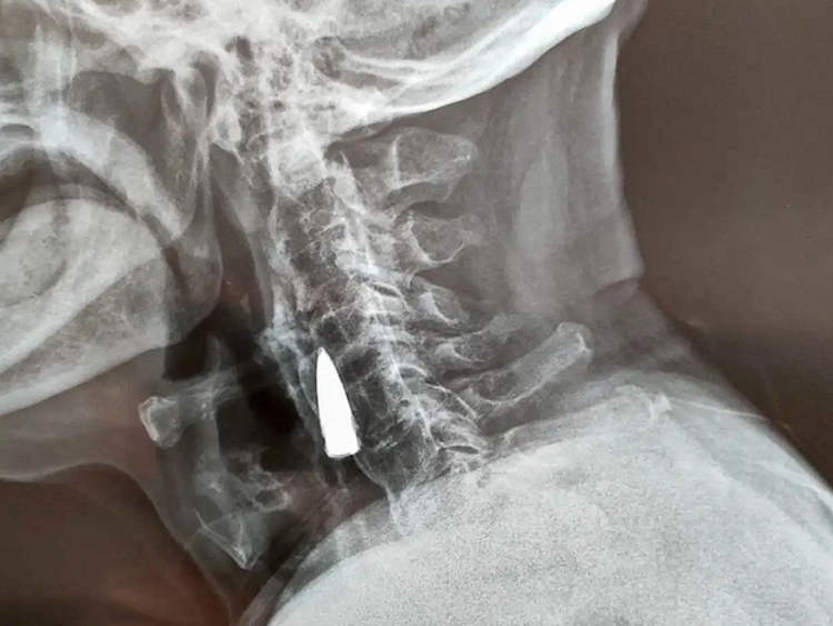

Para ser más exactos, Zhao He se dio cuenta del hallazgo tras acudir al hospital de Linyi, provincia de Shandong, para un examen físico el pasado viernes 21 de octubre. Allí, los médicos encontraron una bala clavada en su cuello cuando le realizaron una radiografía.

De hecho, Zhao estima que la bala podría haber estado en su cuello desde 1944, cuando le alcanzó la bala mientras cruzaba el río. La bala supuestamente entró por el lado izquierdo de la nariz, perforándole la mandíbula superior y arrancándole los dientes antes de alojarse en su cuello.

Sea como fuere, los médicos confirmaron que la misma no le había hecho ningún daño al veterano, incluso después de 77 años. Con todo, los doctores han comunicado que no van a sacar la bala del cuerpo, ya que eso sí podría dañar al veterano, dada su edad. [OddityCentral]